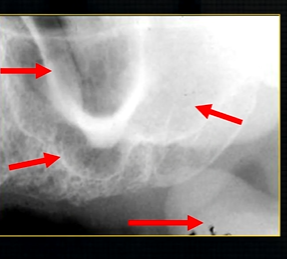

dental radiographic images are 2D representations of the 3D teeth and bones of the skull

soft tissue shadowing, is for the most part, not relevant

resultant radiographs are always 2d demonstrations of a 3d object - all structures, internal and external will be superimposed on one another

how the anatomy is presented geometrically is dependent on the relative positions of the patient, image receptor and the X ray beam

what does this anterior periapical graph show?

oval radiolucent area between the central incisors - is it Infront of the teeth (buccally?) or is it behind them? - you can’t tell radiographically

but its shape and position is compatible with the palatally positioned with the nasopalatine formaina

more posteriorly - radiopacities indicate the nasal septum and floor of the nose

dense, thin , white line in the middle of the image is the nasal septum

less dense opacity is caused by the

inferior nasal concha

radiolucency - nasal septum

lateral wall of the nose

maxillary air sinus

mid-palatal suture

this increased radiopacity is caused by the soft tissues at the tip of the nose - shadow - dense tissue